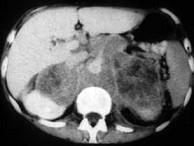

问题 男,76岁,全身浅表淋巴结肿大,请结合下列图片作出诊断 ( )

选项 A、肾上腺转移瘤 B、肾上腺淋巴瘤 C、肾上腺癌 D、肾上腺嗜铬细胞瘤 E、肾上腺腺瘤

答案 B